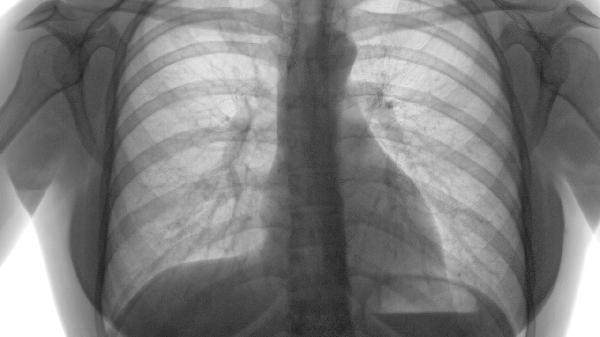

肺气肿是如何引起的

肺气肿的治疗方法包括药物治疗、氧疗和肺康复训练,其病因主要与长期吸烟、空气污染和遗传因素有关。药物治疗常用支气管扩张剂、糖皮质激素和抗生素;氧疗可改善低氧血症;肺康复训练包括呼吸肌锻炼、有氧运动和营养支持。

肺气肿的预防和治疗需要多管齐下,包括戒烟、改善环境、职业防护、遗传筛查等综合措施。早期诊断和干预可显著改善预后,提高生活质量。建议高危人群定期进行肺功能检查,发现异常及时就医,遵医嘱规范治疗。